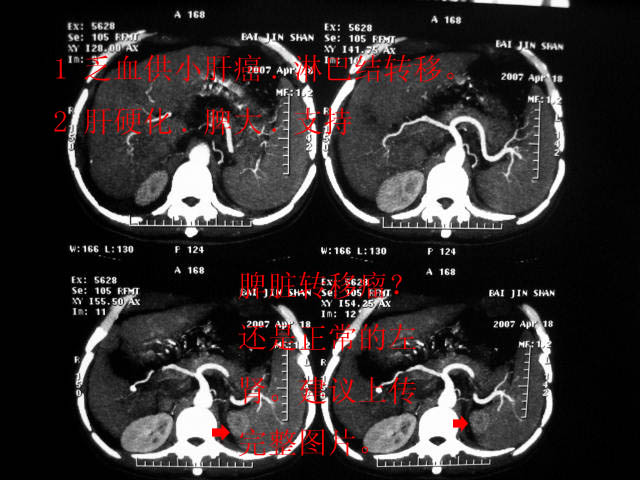

拟;1)乏血供小肝癌.淋巴结转移。

2)肝硬化。

1 乏血供小肝癌.淋巴结转移。

2 肝硬化.脾大.支持!